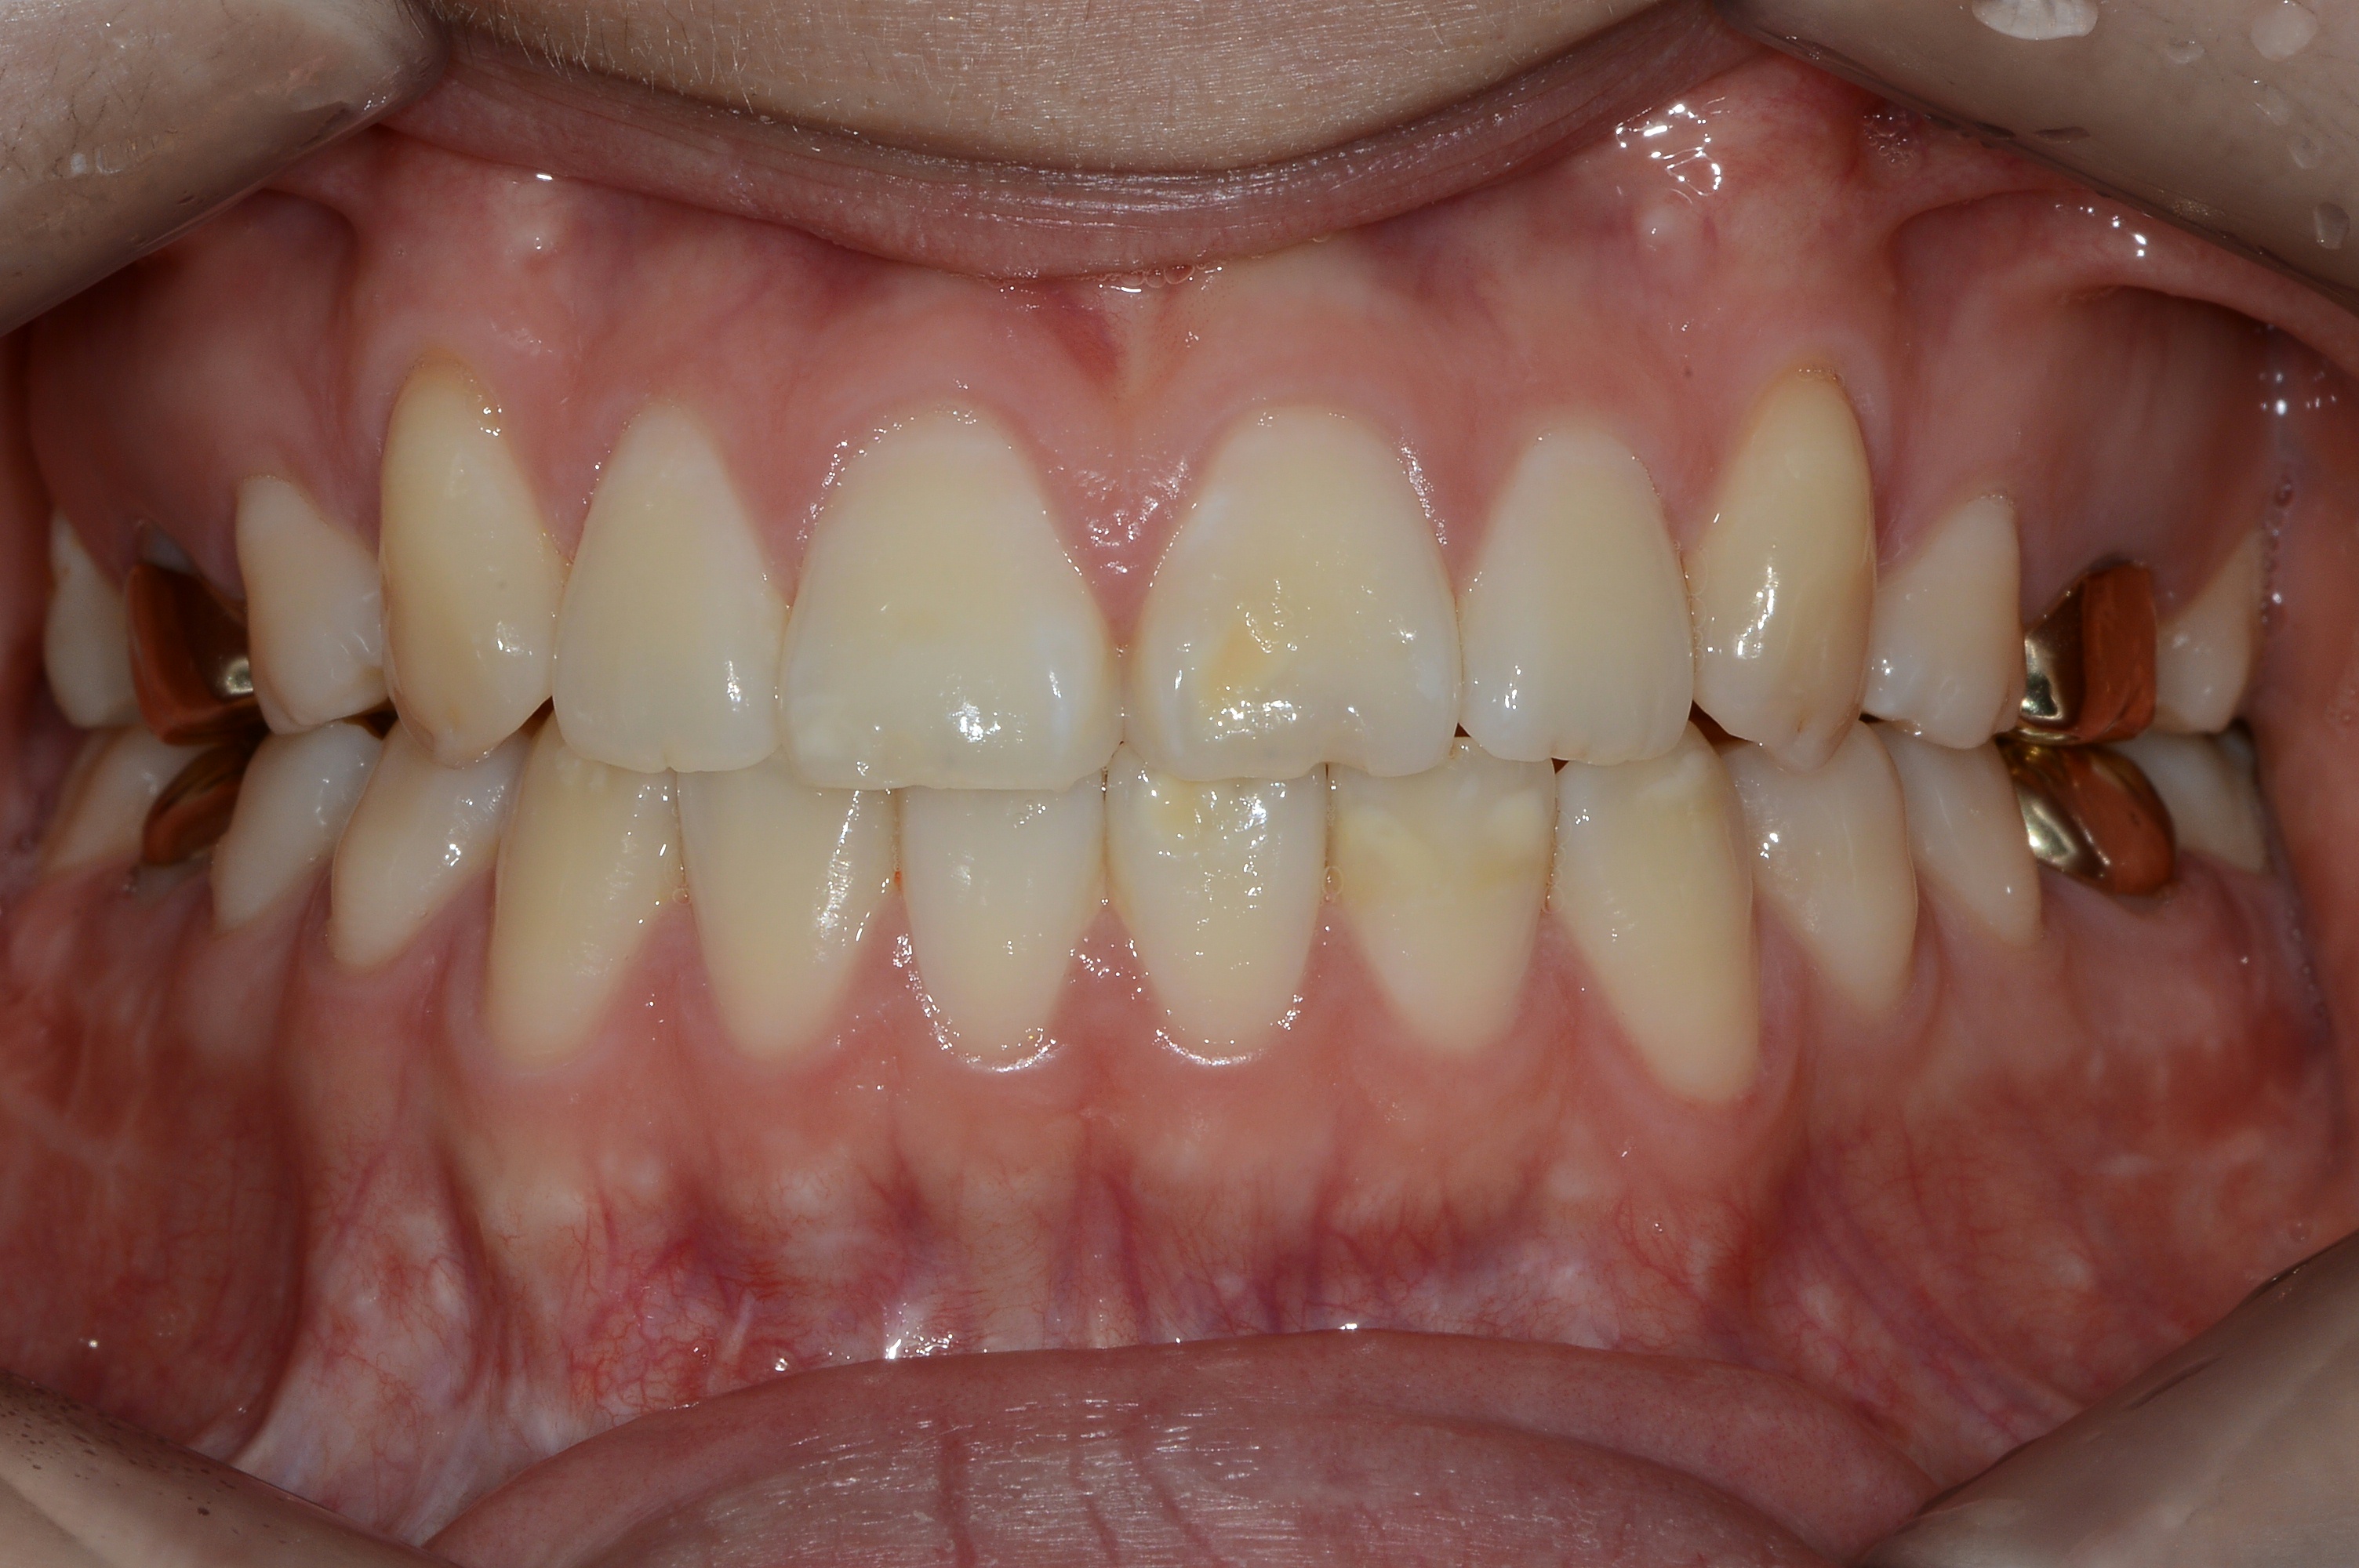

치료 후 사진입니다.